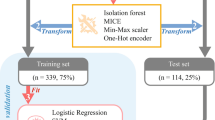

Audiometric thresholds were obtained using a number of different audiometers including Grason-Stadler (GS-10, GS-16), Interacoustics AC-30, Virtual 320 and Interacoustics Equinox, running under the same Harvard Audiometer Operating System (AOS)24. Only pure-tone air-conduction (AC) thresholds measured at standard audiometric frequencies from 0.25 kHz to 8 kHz (in octave steps) using TDH39 headphones or ER-3A insert earphones were considered. Bone-conduction (BC) thresholds were acquired from 250 Hz to 4000 Hz with a Radioear B-71 vibrator over the mastoid. Word recognition was assessed using a recorded CID (Central Institute for the Deaf) W-22 test, consisting of 50 monosyllabic word lists presented with a contralateral masker (speech-shaped noise). The Articulation Index (AI) was used to predict the speech intelligibility curve (SIC, Fig. 1B), a speech intelligibility performance as a function of presentation level based on the audiogram25,26 (Fig. 1A), using a transfer function for CID W-2227. This procedure was automatically generated by the Harvard AOS software as previously described28. The level at which maximal intelligibility was predicted (PBmax) was chosen as the presentation level. If this value, however, fell below 70 dB HL, presentation level remained at 70 dB HL. To assess word recognition deficits that cannot be accounted by a loss of audibility, we measured either (1) the WRS obtained at predicted PBmax and (2) the difference between the measured vs. predicted WRS (∆WRS) as defined by the SIC in each patient (Fig. 1B).

Illustration of the relationship between audiometric thresholds and the performance-intensity function for speech recognition (i.e., speech intelligibility curve). The speech intelligibility curve in (B) is drawn from the amount of speech material that is audible to a patient with a specific hearing loss (A) combined with a transfer function appropriate to the speech material. In (A), W-22 phonetically balanced words presented at either 20 dB HL (green), 60 dB HL (orange) or 100 dB HL (red). To index the loss of intelligibility in word recognition that cannot be accounted by a loss of audibility, we also calculated the difference between the measured word recognition score and the one predicted by the SIC in each patient (B).